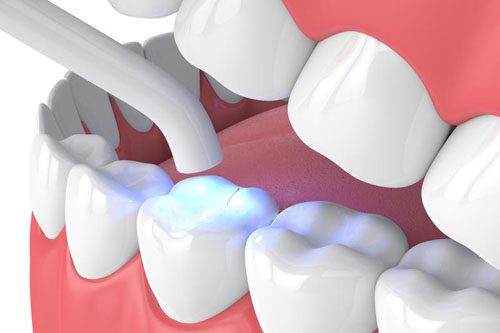

¿Cómo se realiza un blanqueamiento dental?

El blanqueamiento dental se realiza aplicando un gel blanqueador sobre los dientes, que contiene peróxido de hidrógeno o peróxido de carbamida, seguido de una fuente de luz o láser para activar el producto y potenciar su efecto.